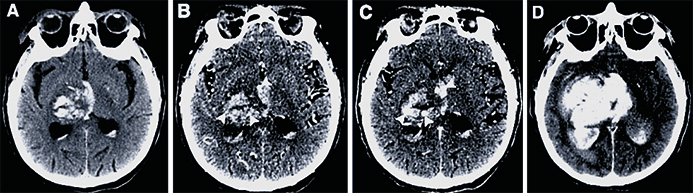

Originalstudie Akut handläggning i Västerbotten jämfört med internationella riktlinjer